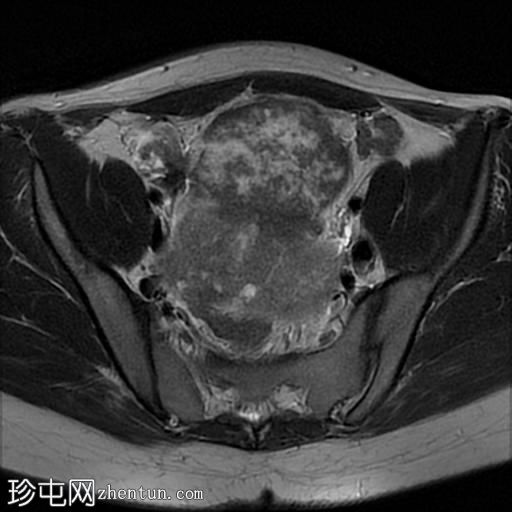

轴位

T2加权像

盆腔内可见多个边界清晰的肿块:

其中一个位于子宫上方,T2加权像呈中等信号,中心区域呈高信号,增强T1脂肪抑制像未见强化。右侧卵巢增大,增厚的血管蒂扭曲,未见强化,轴位和矢状位T2加权像均显示清晰。

另一个位于子宫后窝,T2加权像呈中等信号,增强扫描显示明显强化。

轻度腹腔积液

2个月前进行的MRI检查显示双侧卵巢肿块均有强化,右侧卵巢肿块未见扭转。